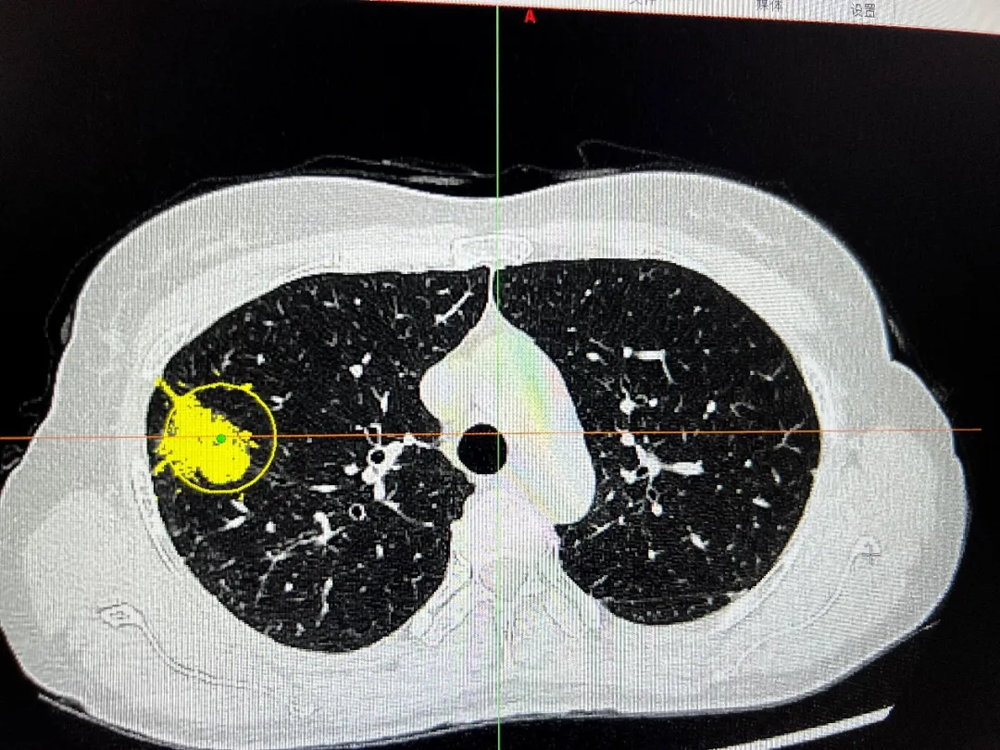

面对恶性程度高、进展快的小细胞肺癌,肿瘤科与呼吸老年科紧密协作。一例伴有广泛转移(肺内、纵隔淋巴结、骨、颈部淋巴结)的晚期小细胞肺癌患者,呼吸科团队迅速完成病理确诊与全面分期。综合考虑患者身体状况与经济因素,为其制定了“化疗联合免疫治疗”的个体化方案。经过系统治疗,患者胸闷、气促等症状显著改善,体力状态恢复,治疗过程平稳。

2025年08月31日CT示:

2025年9月29日CT示:

2025年11月20日CT示: